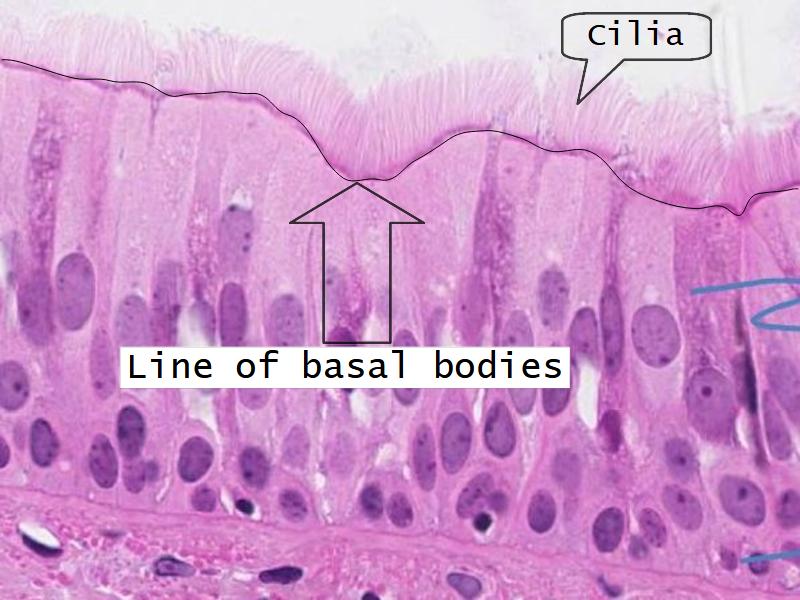

Respiratory epithelium

- Pseudostratified

- Ciliated

- Columnar

- Ciliated columnar cells

- Basal cells